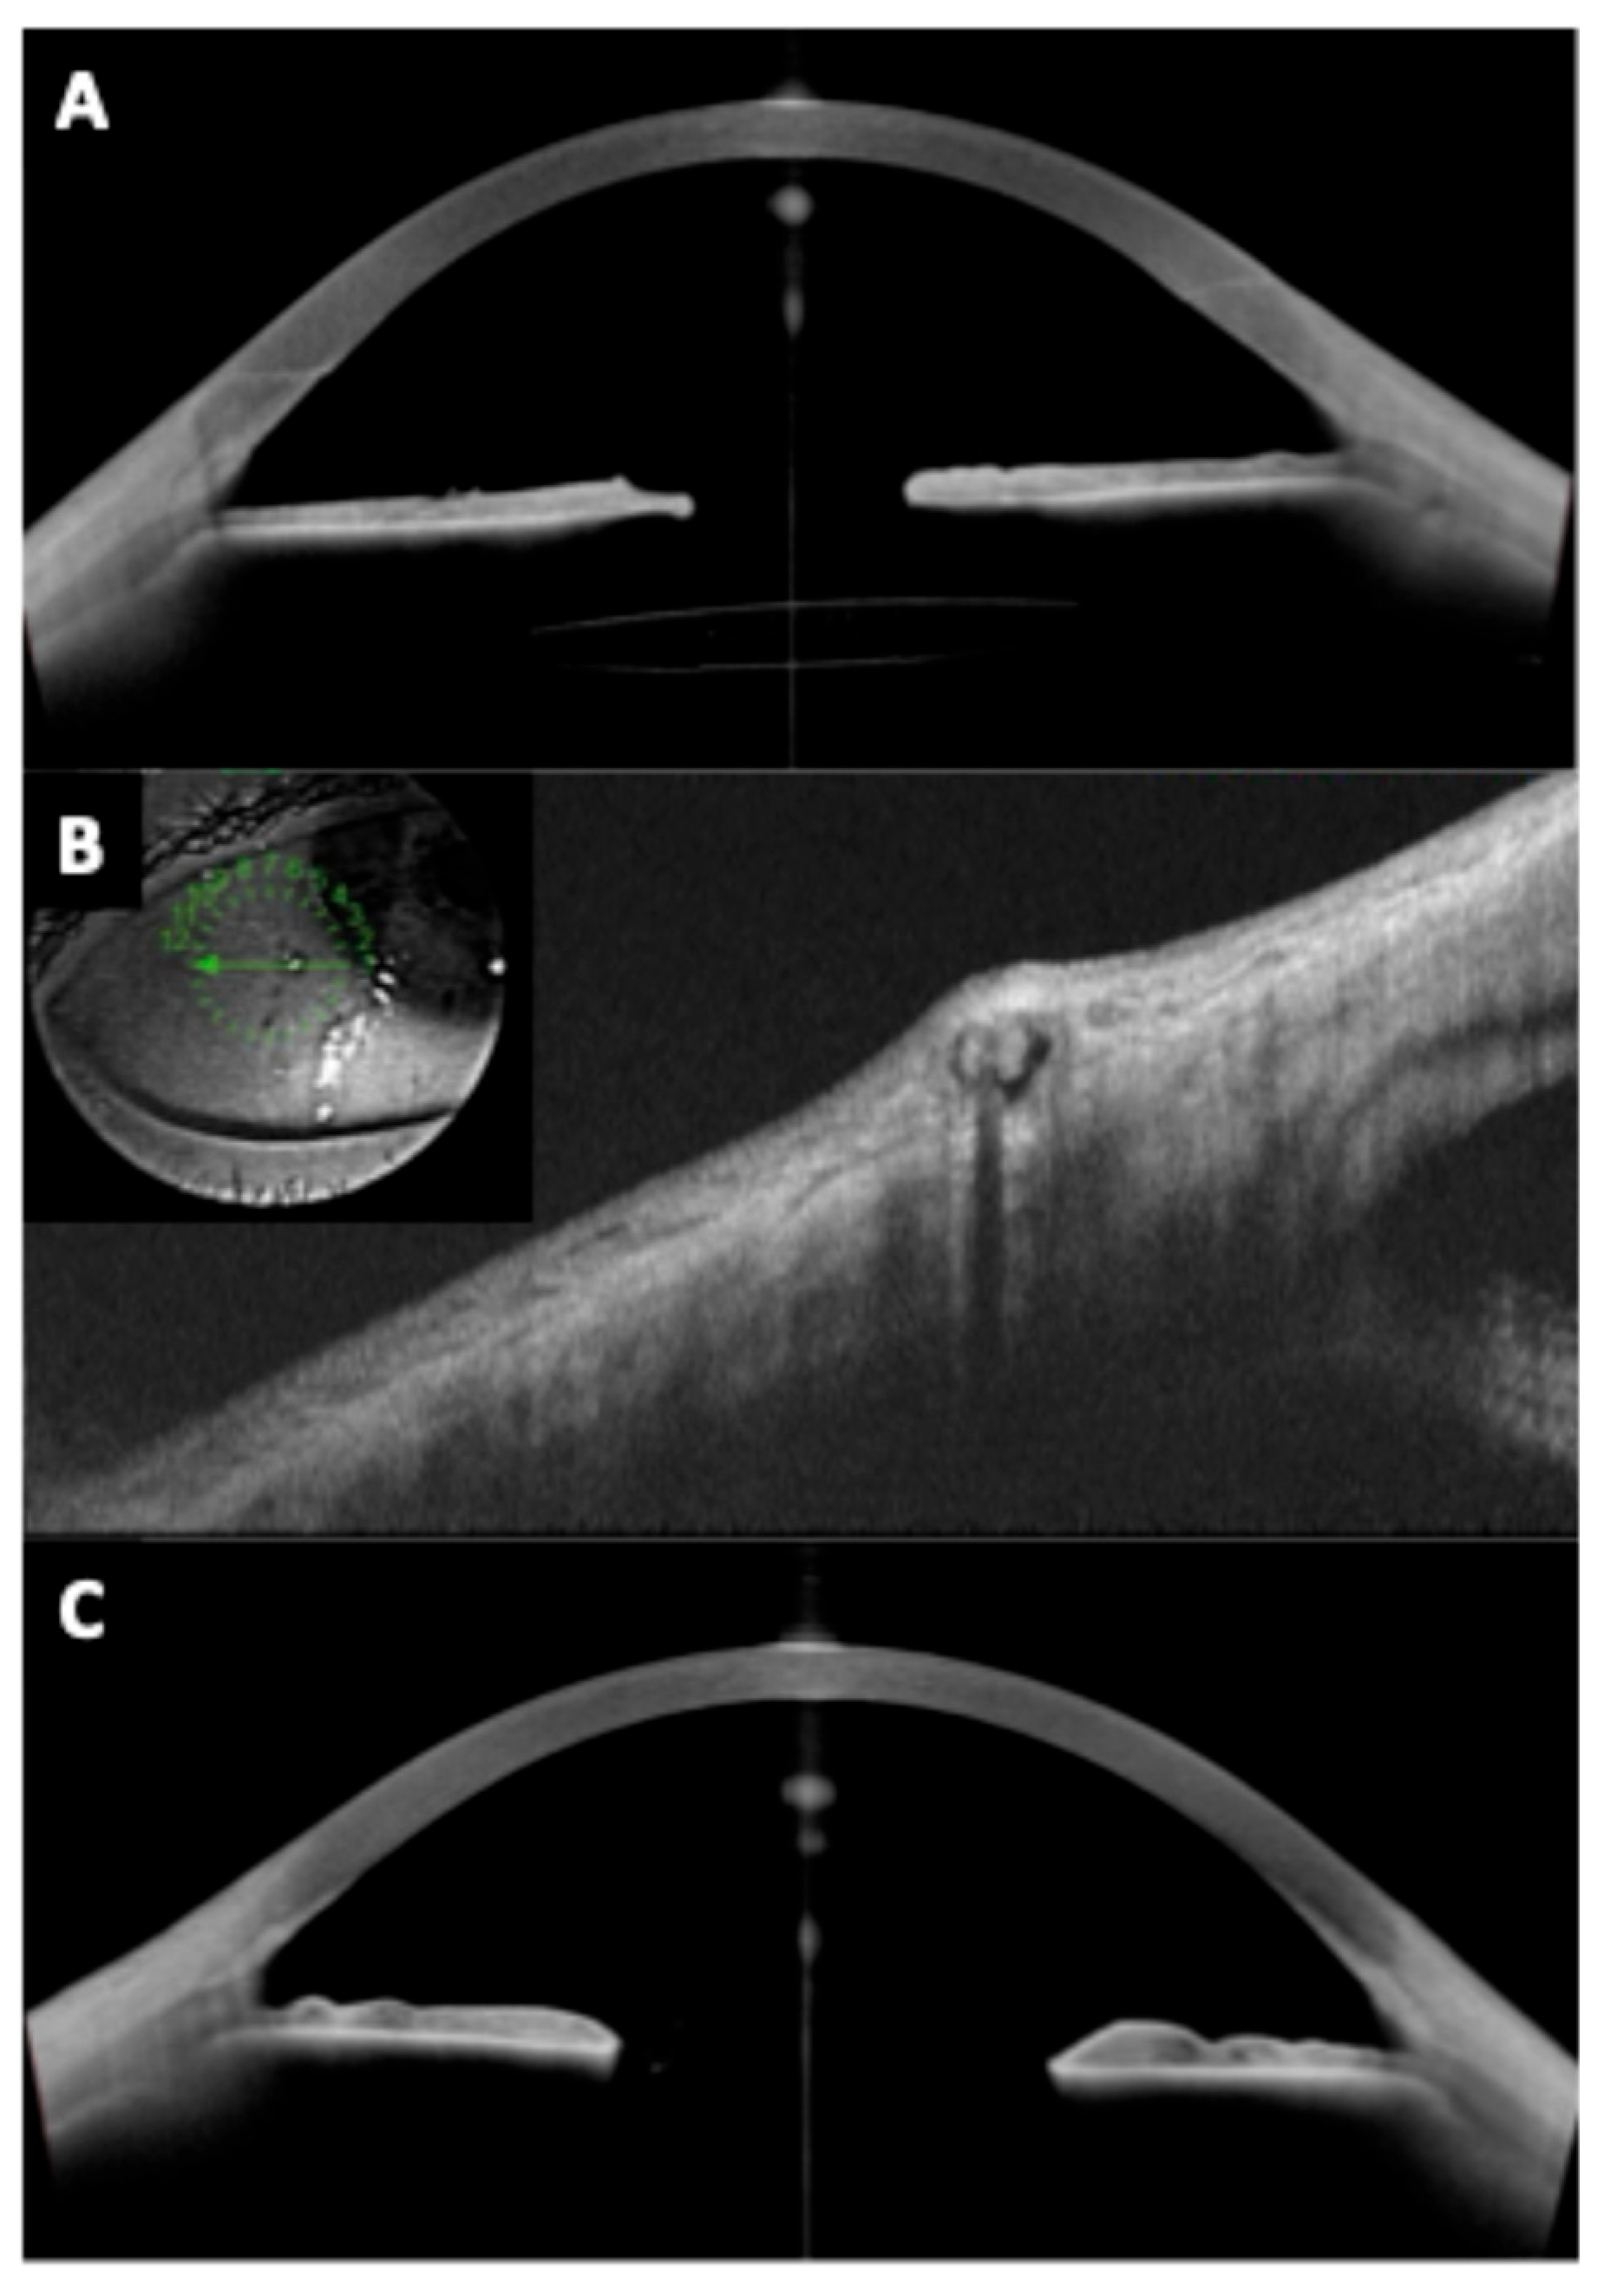

2.3.4. Angle Anatomy

Fourier-domain and swept-source anterior segment OCT can image the iridocorneal angle in detail. After pIOL implantation, angle anatomy often changes: posterior chamber ICLs typically cause a mild reduction in angle width and volume because the iris is slightly pushed forward by the ICL (Figure 2). A study revealed postoperative angle opening distance decreased by ~20–25% after ICL, though the angles generally remained open in appropriately selected eyes [27]. Similarly, our group determined iridocorneal angle changes prospectively in ICL patients, indicating initial angle narrowing of 39–45% which was stable beyond 1 month postoperative [39].

On the other hand, anterior chamber pIOLs (angle-supported lenses) can cause even more pronounced angle shallowing and sometimes focal synechiae formation at the lens footplates, which can be visualized with anterior segment OCT [40,41].

Pupillary block glaucoma is a pIOL-related emergency that occurs when aqueous flow from posterior to anterior chamber is impeded, causing iris bombe (forward bowing of the iris) and acute angle closure. In pIOL patients, this can happen if the PI is blocked, if an ICL without a central port traps fluid or if pigment or viscoelastic obstructs the central port [42,43].

Clinicians have reported using OCT to differentiate pupillary block from other causes of high intraocular pressure. In pupillary block, the OCT shows the iris bowed forward in a classic “iris bombe” convexity contacting the lens or ICL, with a deep posterior chamber and shallow anterior chamber. Anterior segment OCT can confirm iris bombe configuration, even when a hazy cornea or a small pupil limits the gonioscopic view [44]. Anterior segment OCT allows for a precise evaluation of hyperopic ICL cases, which usually present with narrower baseline angles, as well as for monitoring the dynamic changes in vault and angle configuration that occur with miosis and mydriasis (Figure 3 and Figure 4).

Figure 2. Anterior segment optical coherence tomography images of (A) iridotrabecular contact; (B) secondary angle-closure and (C) Anterior synechia secondary to posterior chamber intraocular lens implantation.